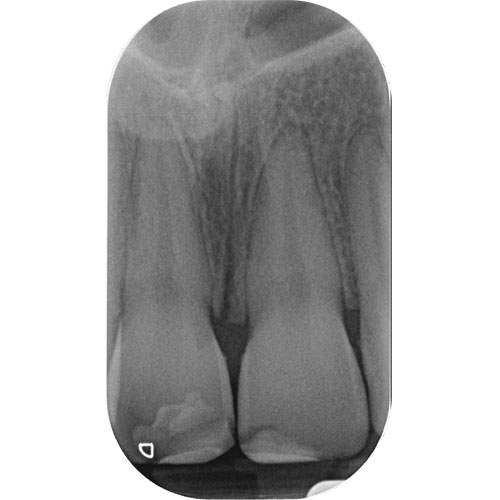

Radiograph: Subluxed UL1 showing normal periodontal ligament space.

Radiographic findings

Of a subluxated tooth will show:

A healthy-looking tooth

No obvious widening or changes in the periodontal ligament.